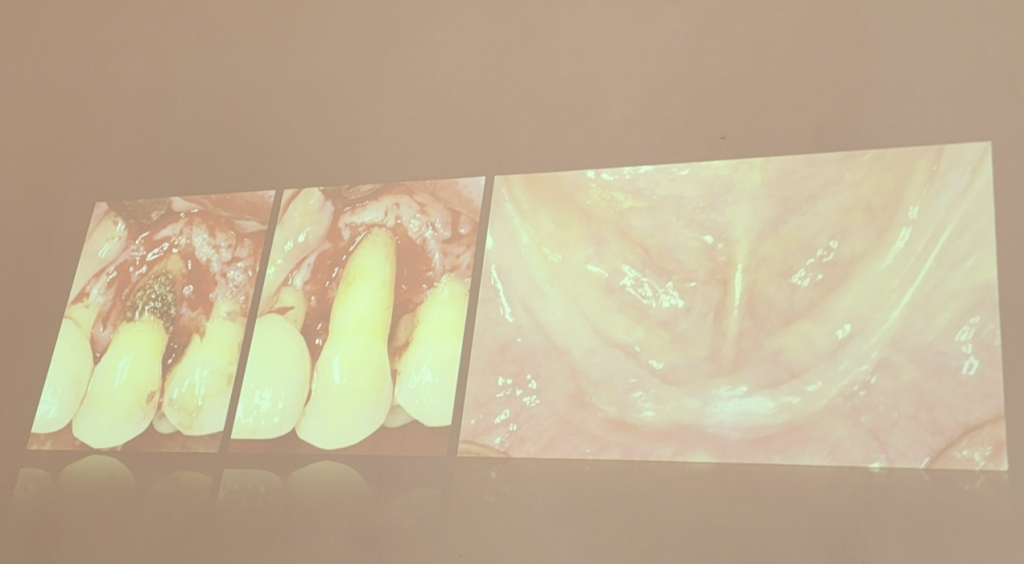

임플란트 수술은 치아·잇몸 건강이 나빠진 사람에게 주어지는 최후의 선택지다. 양치질을 게을리하면 치아와 잇몸 사이에 병원성(독성) 세균이 많이 끼는데, 병원성 세균이 피부·머리를 뚫지 못하는 것과 달리, 몸속으로 침투할 수 있는 유일한 부위가 잇몸이다. 병원성 세균이 잇몸에 달라붙고 제거되지 않으면 치석으로 자리 잡는데, 치석은 한마디로 '세균의 집'인 셈이다. 치석은 잇몸뼈를 계속 녹여 잇몸과 치아 사이의 틈을 벌리고, 치아를 떠받치는 잇몸이 줄어들면서 결국 치아가 흔들리거나 빠진다. 치아가 빠지면 잇몸뼈도 줄어들어, 틀니를 착용해도 덜그럭거리는 사태가 벌어질 수 있다.

치아·잇몸 질환을 방치해선 안 되는 이유다. 정 교수는 "치아와 잇몸의 벌어진 틈새는 세균의 입구로, 세균이 잇몸을 통해 피를 걸쭉하게 만들어 전신 만성 염증, 혈관질환을 일으킨다"며 "치주질환을 오래 방치하면 류머티즘성 관절염, 당뇨병, 비만, 골다공증, 조산, 저체중, 치매, 폐 질환, 심혈관질환 등을 유발할 수 있다"고 경고했다. 심지어 치매를 유발하는 원인 중 콜레스테롤보다 더 나쁜 게 치주질환이라는 게 그의 설명이다.